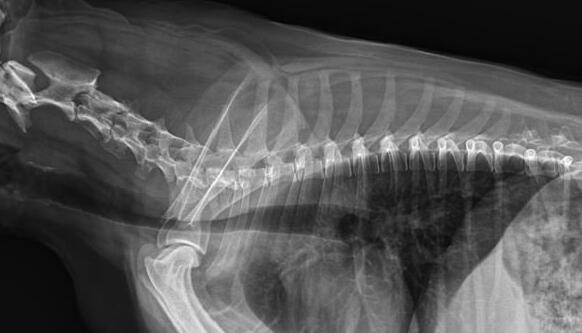

利用寵物dr拍攝圖像效果圖

1、DR的DQE檢測效率可達(dá)74%,而傳統(tǒng)普通膠片組合X線照片DQE為30%。

2、寵物DR成像速度快,采集時間10ms以下,成像時間僅為3秒,對于受傷的寵物來說,檢查越快速,越能早點(diǎn)幫助其治療,降低痛疼。對于寵物主人而言,也是一種心理安慰。

3、數(shù)字圖像可進(jìn)行后處理。圖像后處理是數(shù)字圖像的很大特點(diǎn)。只后要保留原始數(shù)據(jù),就可以根據(jù)診斷需要,并通過軟件功能,有針對性的對圖像進(jìn)行處理,以提高診斷率。

4、獸用dr所具備的輻射劑量較低,相比傳統(tǒng)的ct而言,對于寵物和醫(yī)生而言,都是一種保護(hù)。